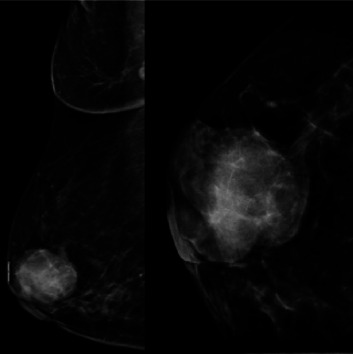

Primary neuroendocrine tumors (NETs) predominantly affect postmenopausal women. This case study focused on a 54-year-old woman who presented with a painless right breast lump. While the lump exhibited estrogen and progesterone receptor (PR) positivity, it lacked human epidermal growth factor receptor 2 expression. Further evaluation revealed positivity for the neuroendocrine markers chromogranin A (CGA) and synaptophysin (SYN). It also revealed a 3% positive Ki-67 proliferation index. Treatment for neuroendocrine breast cancer (NEBC) mirrors that of standard invasive breast cancer: breast conservation or mastectomy combined with sentinel lymph node biopsy or axillary dissection. The patient underwent a right mastectomy with sentinel lymph node biopsy, followed by hormonal therapy based on her tumor's immunohistochemical profile. Due to the low incidence and limited research on primary NETs, their exact origin remains shrouded in mystery. Accurate diagnosis, specific treatment options, and long-term prognosis remain significant challenges in managing this rare form of breast cancer.